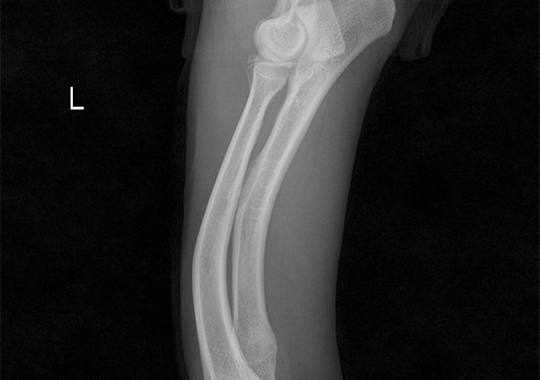

요척골 복합만곡기형 수술 전

요척골 복합만곡기형 수술 후